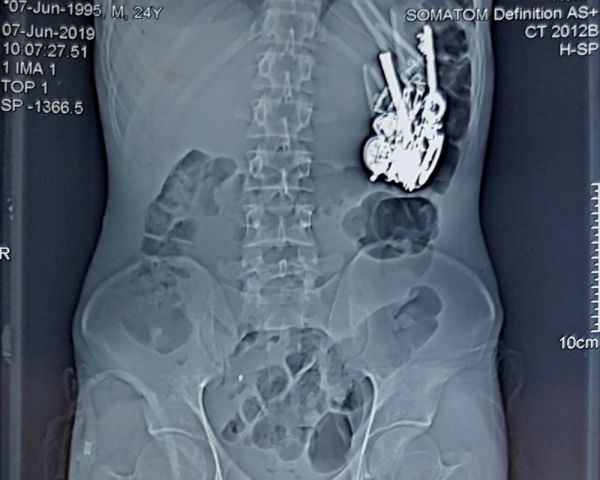

Во время операции хирурги извлекли из Руни целый клад: 69 цепочек, 80 сережек, 46 монет, 8 кулонов, 11 колец для носа, 4 ключа, 5 ножных браслетов и 1 циферблат. Все это добро девушка таскала из дома и магазина брата. Все попытки семьи выяснить у Руни, куда пропадает ювелирка, заканчивались ее рыданиями.